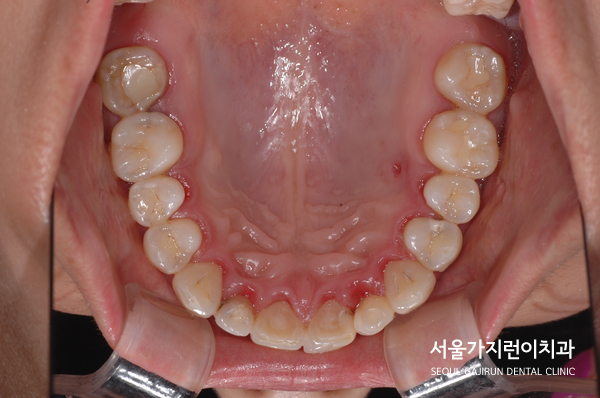

환자분의 경우에는 대구치가 손실된 것을 사진처럼 볼 수 있었는데요. 네 곳의 발치 공간을 임플란트 없이 닫는 것을 희망하고 계셨습니다. 여기에 입을 다물었을 때 아랫입술이 나와보이는 주걱턱 성향을 갖고 있어 앞니가 거꾸로 물리는 듯한 모습도 발견할 수 있었는데요.

결국 환자분이 원하는 것처럼 설측교정방식을 이용한 치아교정을 진행했으며 공간의 폐쇄와 더불어 사랑니를 세워 어금니로 활용할 수 있게 만들었는데요. 교정을 마친 후를 보면 정상교합으로 달성된 것을 확인할 수 있으며 발치로 인한 공간을 잘 폐쇄하였습니다. 여기에 주걱턱 느낌도 교정을 마쳤는데요. 모든 케이스에 적용가능한 것은 아니지만 상기 환자와 비슷한 사랑니 치아교정이 고민된다면 교정전문치과 서울가지런이치과 교정과 의원을 방문해보시기 바랍니다.